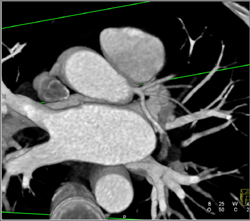

Diseased LAD